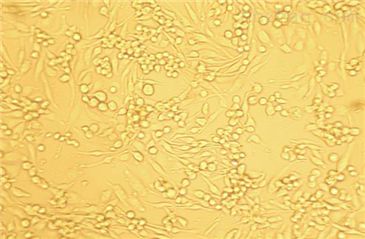

- 生长状态:

贴壁生长

1590(人乳腺癌细胞)复苏